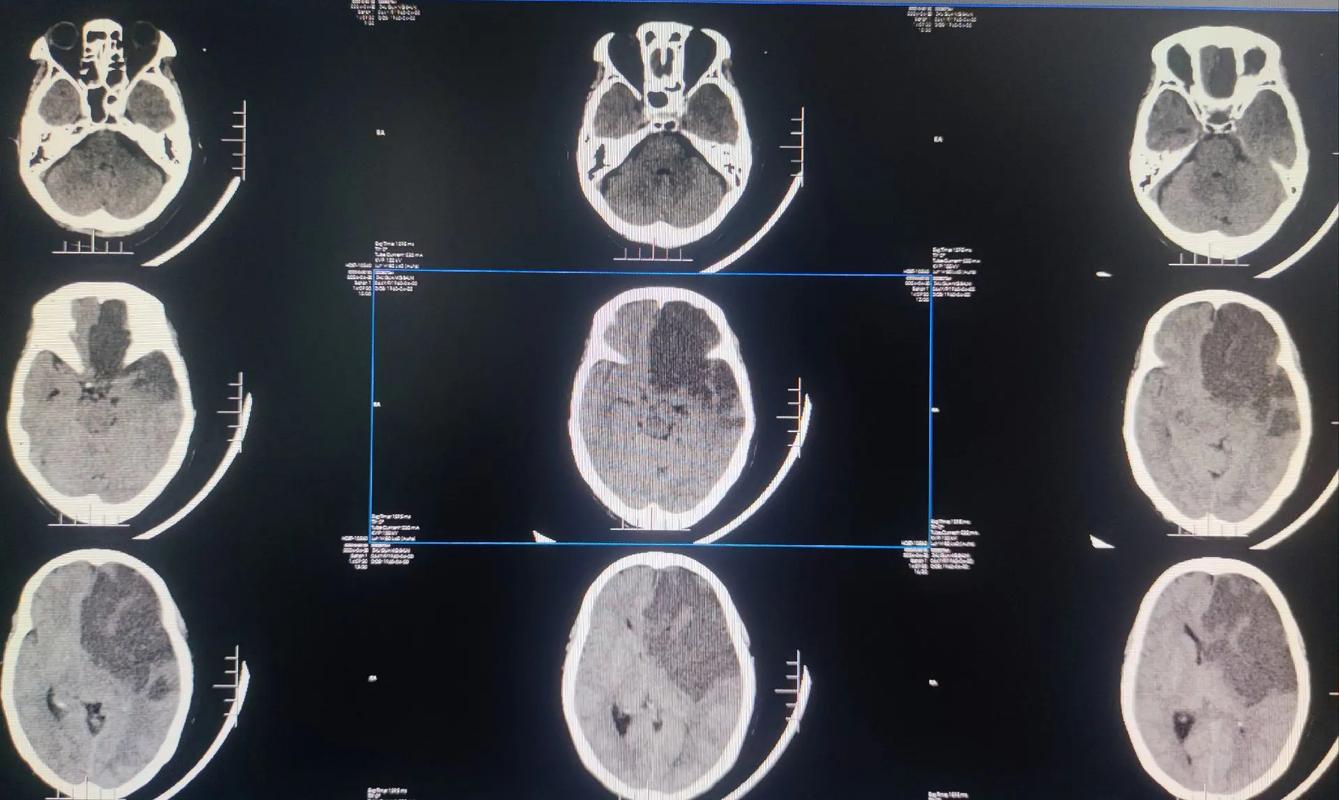

- 当时的梗塞部位和大小? 通过头颅CT或MRI可以明确,这决定了当时出现的症状(如偏瘫、失语、偏身感觉障碍等)和可能留下的后遗症。

- 头颅CT或MRI: 了解脑部有无新的梗塞灶或陈旧梗塞灶的变化。